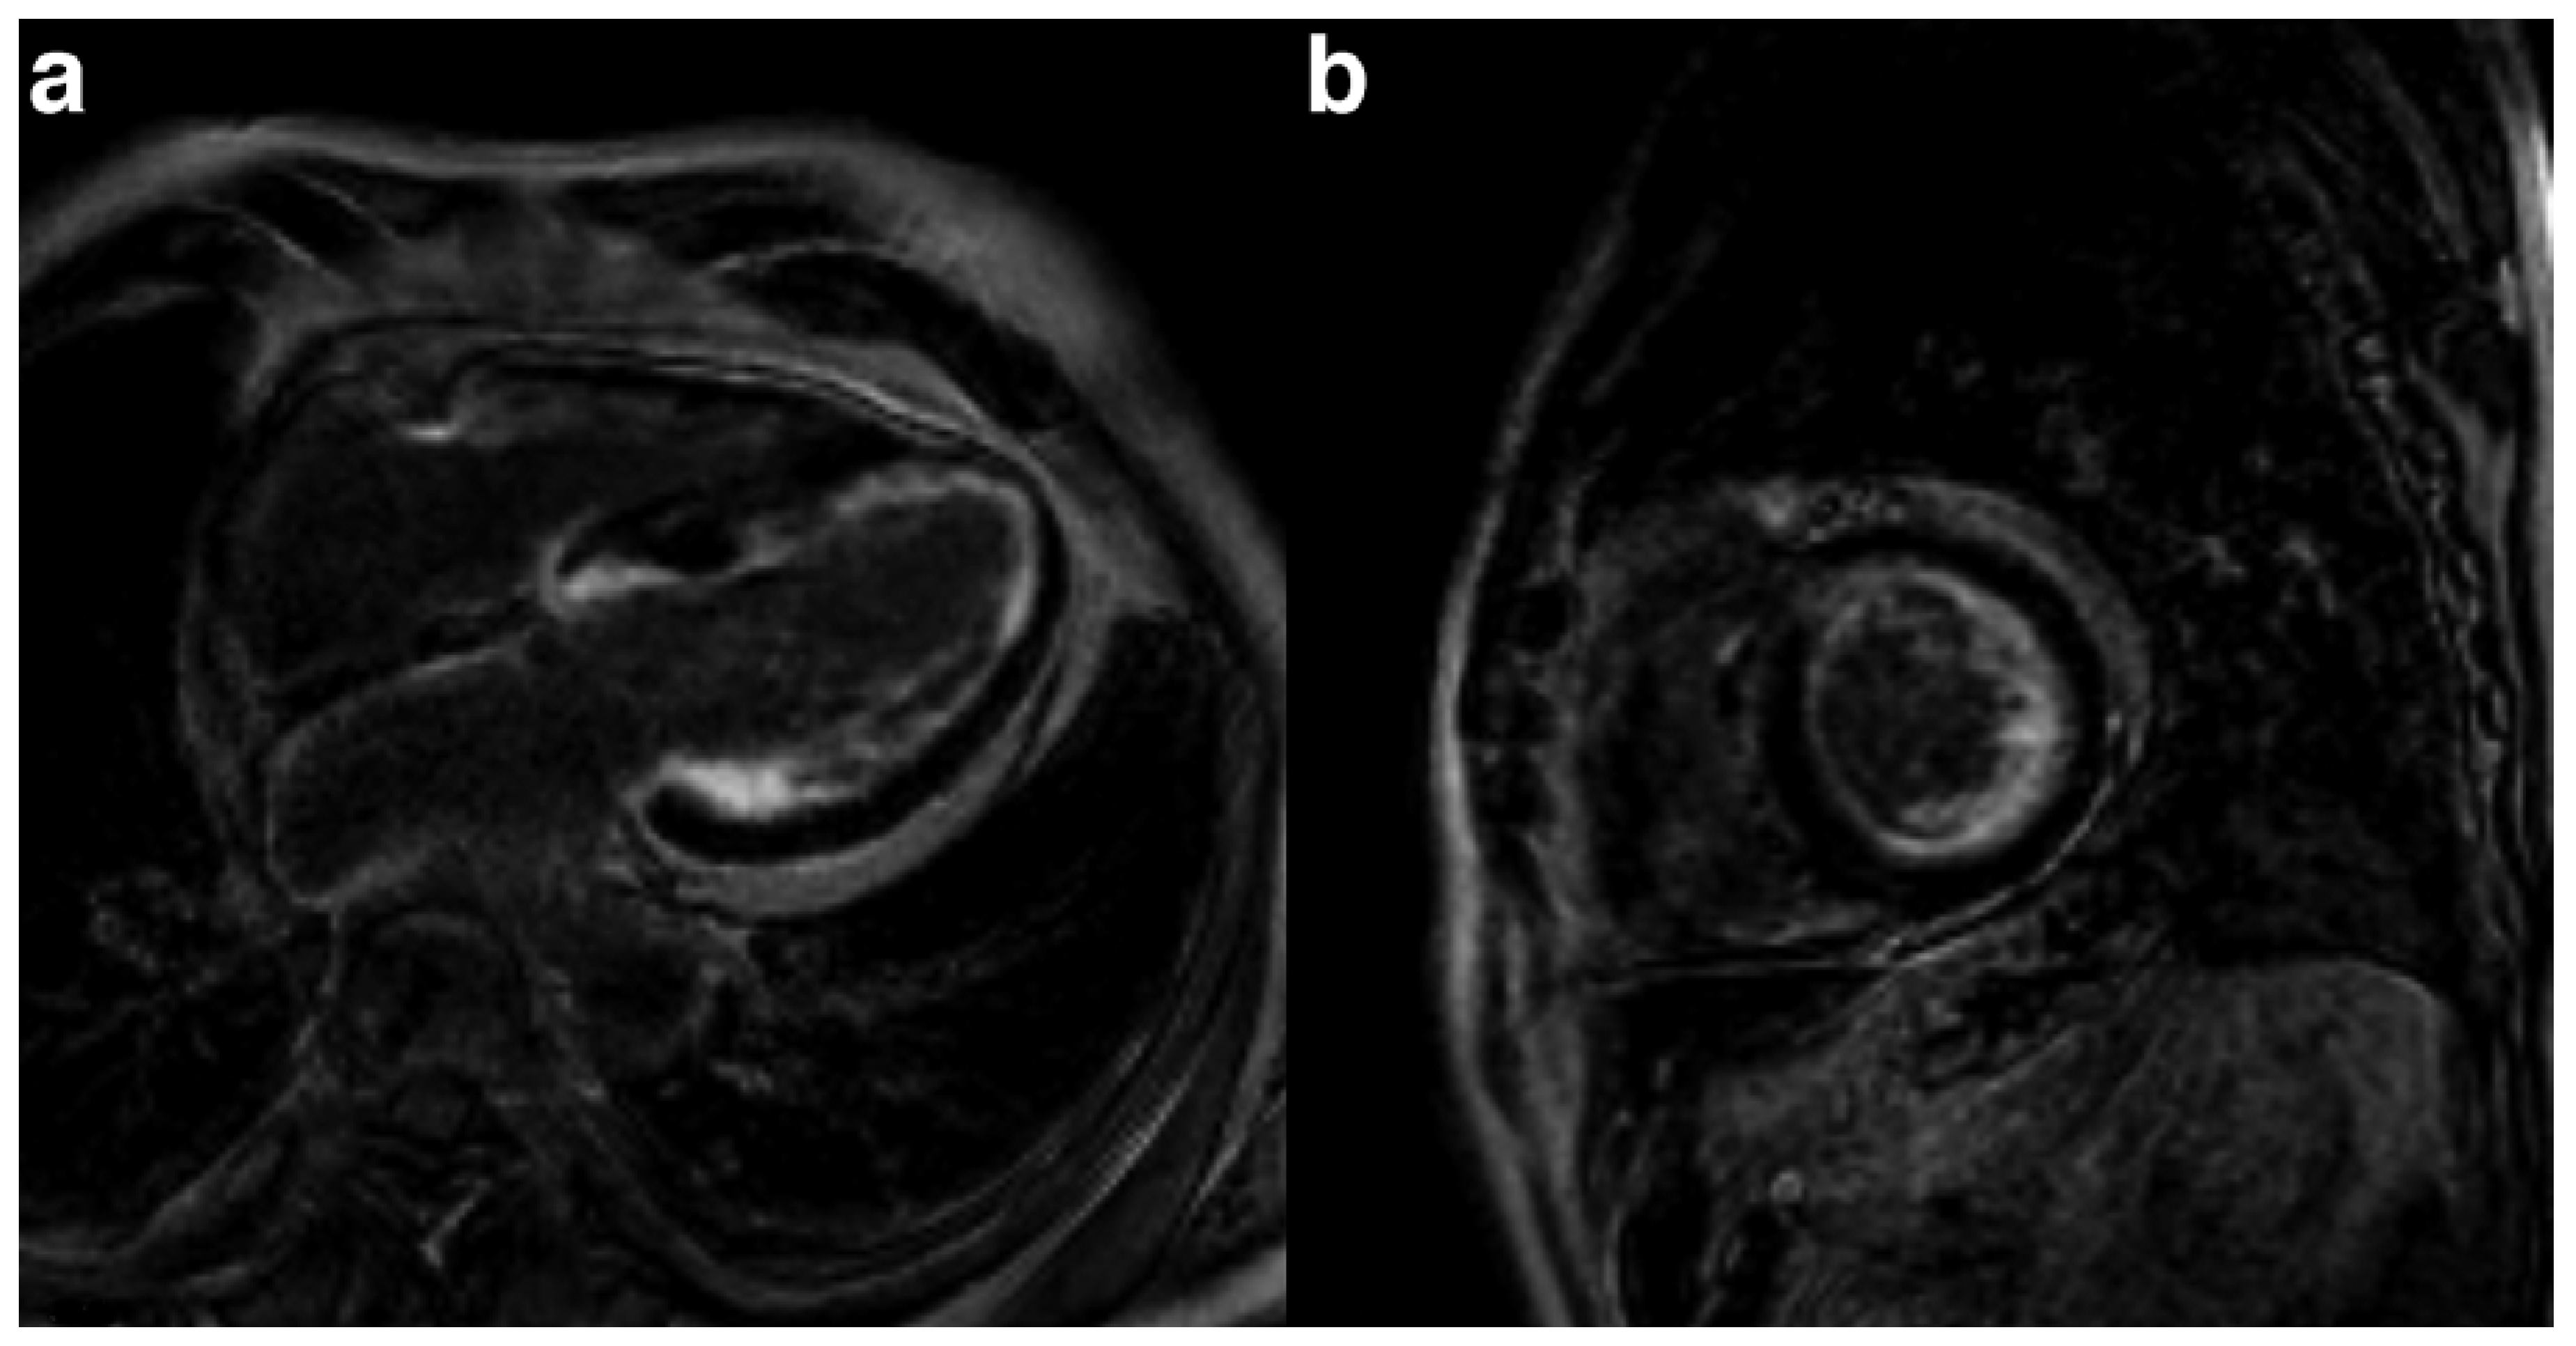

For all types of cardiac amyloidosis, cardiac MRI offers the possibility to evaluate ventricular wall thickening and mass, and diastolic and systolic function, as well as to detect amyloid depositions, visualised by diffuse late gadolinium enhancement (Figure 5). The slower wash in and wash out of gadolinium is due to expansion of the extracellular space, which is typical for amyloid. Typically, the pattern of late gadolinium enhancement is diffuse and patchy.

Figure 5. cMRI example of late gadolinium enhanced images demonstrating diffuse late gadolinium enhancement in the left ventricular myocardium and to a lesser extent even in the left atrial myocardium.